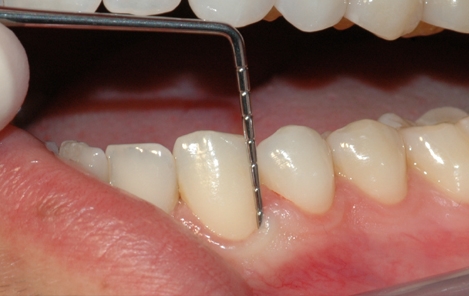

Tannstensfjerning, puss og poléring

Etter undersøkelsen er det vanlig at tannlegen eller tannpleieren fjerner tannsten og misfarging fra tennene.Tannsten består for det meste av kalkstoffer fra spyttet som avleires og legger seg på tannflaten som et hardt belegg. Det sitter så godt fast at det er nærmest umulig å fjerne på egen hånd med tannbørsten.

Tannlegen eller tannpleieren har derimot mulighet til å fjerne både tannsten og overfladiske misfarginger ved å rense, pusse og polere tennene. Tannstenen fjernes enten med maskin eller ved å skrape den bort med håndinstrumenter. Misfarginger kan poleres bort med en spesiell pussepasta som inneholder ekstra slipemiddel. Alternativt går det an å benytte saltblåsing for å fjerne misfargingene.